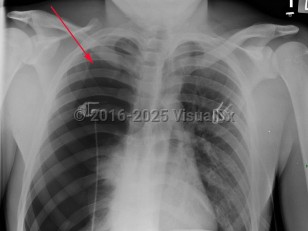

Spontaneous pneumothorax (SP) is caused by the introduction of air between the visceral and parietal pleura, typically as the result of trauma. SP can be classified as either primary or secondary. The presence or absence of lung disease distinguishes the primary form from the secondary form. Primary SP (PSP) lacks underlying lung disease, whereas secondary SP (SSP) patients have a preexisting condition such as chronic obstructive pulmonary disease (COPD; a majority of cases), cystic fibrosis, pulmonary infection, interstitial lung disease (especially histiocytosis and sarcoidosis), AIDS, neoplasms, or drug use.

The size of the pneumothorax, rate of development, and underlying clinical status determine the clinical presentation. Those with a mild PSP may not seek care, while those with SSP present acutely. The range of signs and symptoms include acute pleuritic chest pain (localized to the side of the pneumothorax), dyspnea, decreased breath sounds, tachypnea, tachycardia, hyperresonance, unilaterally decreased lung sounds, or acute decompensation.

Tension pneumothorax (TP), while rare, may result from an SP. TP, a life-threatening condition, is caused by pressurized air in the pleural space that displaces mediastinal structures and compromises cardiopulmonary function.